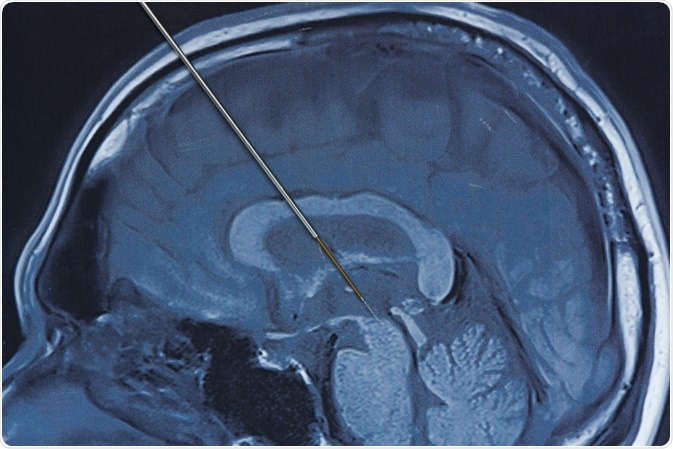

A local or general anesthetic is usually used while implanting the leads into the brain. A small hole is drilled into the skull, and the electrode lead is inserted stereotactically into the intended area of the brain. If the symptoms are primarily evident on the left side of the body, the lead will be placed on the corresponding right side of the brain and vice versa.